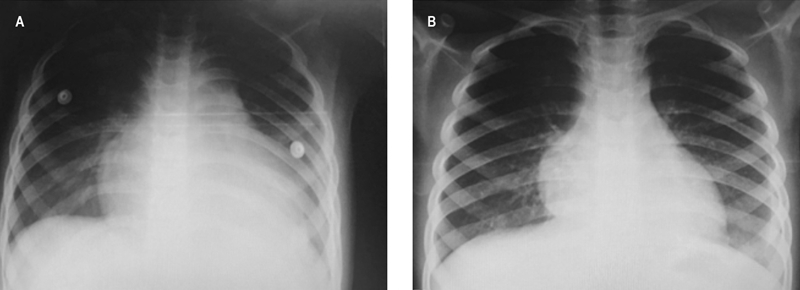

Dos días después, el cuadro progresó a tos seca, dolor abdominal epigástrico opresivo, vómitos gastroalimentarios y fiebre. Fue tratada con antipirético y amoxicilina (50 mg/kg/día), sin mejoría, por lo que se añadió antiespasmódicos. Por empeoramiento del dolor precordial se realizó radiografía de tórax que evidenció cardiomegalia (figura 1) y por ecocardiograma se identificó derrame pericárdico.

Figura 1 A) Radiografía anteroposterior de tórax al ingreso hospitalario. Se observa cardiomegalia y borramiento de ángulos cardiofrénicos. B) Control radiográfico anteroposterior de tórax después de la pericardiocentesis.

La paciente fue ingresada al Departamento de Urgencias del Hospital Pediátrico de Sinaloa, Culiacán, Sinaloa, México, con disnea de medianos esfuerzos en posición sedente, discreta plétora yugular, sin cianosis ni pulso venoso; a la auscultación se percibió frote pericárdico. En una nueva radiografía de tórax se detectó cardiomegalia (índice cardiotorácico de 0.65). El electrocardiograma demostró elevación difusa de segmento ST, por ecocardiograma (figura 2) se encontró derrame pericárdico (aproximadamente 200 mL). Se realizó pericardiocentesis y se extrajeron 140 mL de líquido de aspecto citrino, con características de trasudado (cuadro 1). Se inició tratamiento con ácido acetilsalicílico (3 mg/kg/día) y antibióticos (cefotaxima y vancomicina) por sospecha de etiología infecciosa.